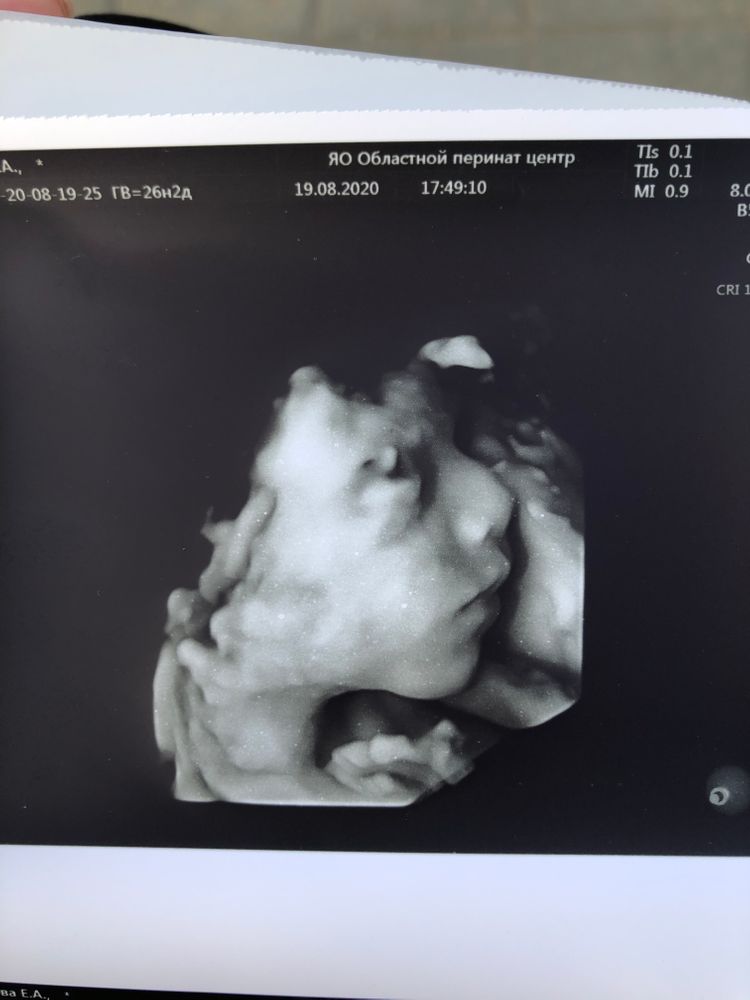

Все будет видно) но мне узист советовал в 28) там уже прям человек))мы почти в 27 делали если считать по 1 скринингу. Очень долго пытались выловить лицо,сынуля каждое узи показывает писюн)))личико прячет. Мы не пожалели,что сходили 😍нам понравилось. Он там зевал,показывал язык )))ну и складывал на лицо все,что можно..ручки,ножки,пуповину)))

УЗИ, КТГ, доплерЗаписалась на межскрининговое УЗИ , по сроку будет ровно 26 недель. Делала второй скрининг в 20, третий будет в 32. А это ,хочу сделать ,чтоб посмотреть как у нас дела )

И хочу пойти не на обычное, а на 4д. В предыдущие разы делала только обычные. А тут хочу на такое сходить. Кто делал? Стоит ли оно того? И как по сроку ? Видно нормально будет?